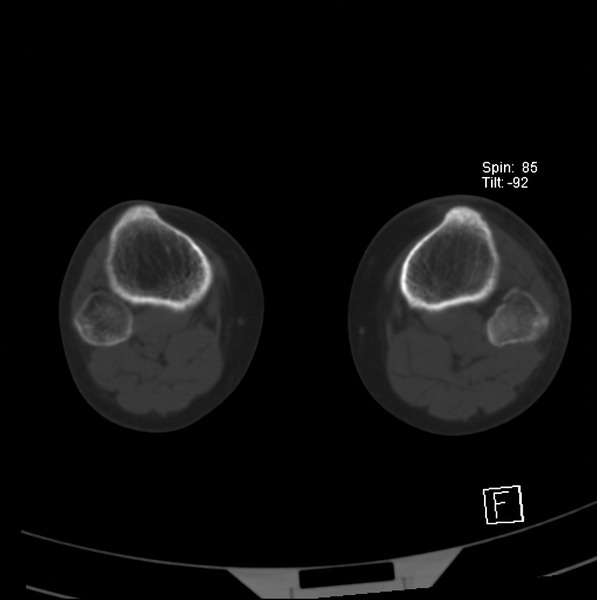

标题: CT21917:右腓骨小头是否骨软骨瘤? [打印本页]

标题: CT21917:右腓骨小头是否骨软骨瘤?

女、43.

不是骨软骨瘤,“牵拽征”,正常变异。有平片吗?

正常变异,“牵拽征”,比目鱼肌牵拽.